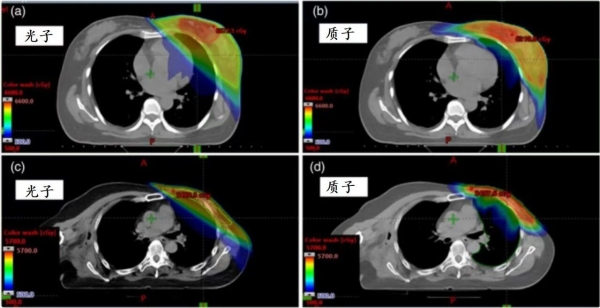

▲ 乳腺癌光子放疗(左)与质子放疗(右)的计划对比,可以看到质子放疗的剂量分布更加“集中”,周边的心、肺等正常器官受照剂量和范围小一些[1]。